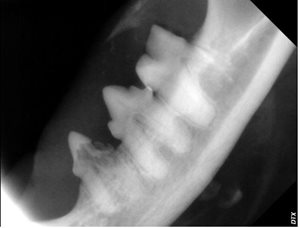

Another lovely feline friend, eight-year-old “Sir Ruby” had dentistry with us last month. During his annual health exam in May 2018, we observed that his teeth were moderately dirty, but by August 2018 there was significant suspicion of resorptive lesions noted by the veterinarian during a routine dental examination. The doctor noted the tell-tale red spot and significant gingivitis associated with his lower premolars. A dental procedure was recommended. During Sir Ruby’s dental surgery, gentle dental probing confirmed crown resorption and associated oral pain. X-rays of the affected teeth confirmed root resorption, as well. The teeth were extracted, Sir Ruby recovered quickly and is back to his normal happy self.

The speed in which this condition can progress, as shown in Sir Ruby’s case, is often surprising- and very much supports the importance of regular dental care and checkups. Please call Coxwell Animal Clinic and book your dental examination today!

Right Lower Premolars